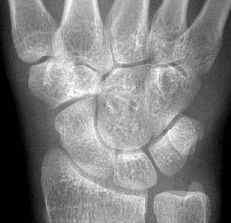

正常腕关节正射影像

X线测量:尺骨变异在标准后前位X线平片上测量,采用Gelberman等的平行线法(尺骨关节面平行线与乙状结肠切迹最远关节面平行线的位置距离差)。

1.尺骨比桡骨长,为正变异;

2.尺骨短于桡骨为负变;

3.两者的平等是中性变异。

症状严重者和常规X线前后位尺骨变异阴性或中性者,握拳旋转手腕拍照。